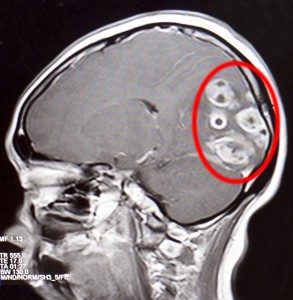

BVXA – PHẪU THUẬT THÀNH CÔNG U NÃO ĐA Ổ

Ngày 04/01/2016, Khoa Ngoại Thần Kinh Bệnh viện Đa Khoa Xuyên Á (BVXA) phối hợp cùng ê kíp Khoa ngoại Thần Kinh Bệnh viện Chợ Rẫy đã phẫu thuật thành công u não đa ổ cho bệnh nhân Trần Thị Tuyết M. (42 tuổi, ngụ tại xã Tân Phú Trung, huyện Củ Chi, TP. Hồ […]